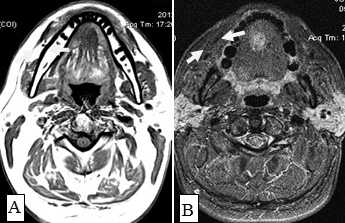

После введения контрастного вещества все опухоли показывали усиление сигнала. При локализации опухолевого процесса в области языка (12 пациентов) границы опухоли визуализировались более четко. В режиме Т2-ВИ опухолевые узлы проявлялись более высокой интенсивностью сигнала, чем у окружающих мышц (рис. 8).

Сложно было с помощью МРТ визуализировать опухоли любых размеров с поверхностным распространением, не выходящие за пределы слизистой оболочки. Опухоли малых размеров (Т1 стадия) в 2 наблюдениях были однородны, не имели центральной зоны некроза и сливались с мышцами. С увеличением размера опухолевого узла отмечалась неоднородность структуры. В наших исследованиях удалось выявить небольшие опухоли Т1 и Т2 стадий, локализованные в области языка и дна полости рта. В 9 наблюдениях опухоли Т2 стадии, не накапливающие контраст при МСКТ исследовании, хорошо визуализировались при МРТ в режимах Т2-ВИ, STIR, проявляясь сигналом высокой интенсивности. Можно было четко видеть границы опухоли и оценить ее размеры (рис. 9,10).

Рис. 8. Пациент П., 76 лет. МРТ полости рта в сагиттальной проекции в режиме Т2-ВИ. Опухоль языка, высокая интенсивность сигнала на фоне окружающих мышц (стрелки)

Рис. 9. Пациент А., 66 лет. МРТ дна полости рта в сагиттальной проекции в режиме Т2-ВИ. Опухоль дна полости рта размерами 2,0х1,8 см с распространением на основание языка Т1N0M0 (стрелки). Границы опухоли четко визуализируются, структура однородная

Не возникало сложностей в выявлении опухолевых узлов Т3, Т4 стадий, имевших все отмеченные выше признаки в различных сочетаниях в 36 исследованиях (рис. 11). Из 50 обследованных с помощью МСКТ и МРТ пациентов у 26 (52,0%) были выявлены метастазы в лимфатических узлах шеи. Поражались преимущественно лимфатические узлы I-II уровня. Признаками метастаза плоскоклеточного рака в лимфатических узлах были: увеличение размера лимфатического узла более 1,0 см, изменение формы лимфатического узла с бобовидной на округлую, структурные нарушения в узле, нечеткость наружных контуров узла, уплотнение окружающей жировой ткани на КТ или изменение сигнала на МРТ.

Рис. 10. А. Пациент Е., 52 года. МРТ полости рта, ротоглотки в аксиальной проекции, Т1-ВИ. Опухоль языка небольших размеров, границы визуализируются с трудом за счет перифокального отека (стрелки); В. Тот же пациент. МРТ в аксиальной проекции, Т2 с подавлением сигнала от жировой ткани. Визуализируются границы опухолевого узла, размеры опухоли языка четко определяются (стрелки)